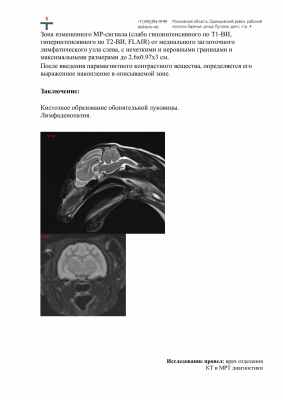

И съездили с ней на прием к Лабынцевой - офтальмолог и терапевт. Кроме того, сделали ей МРТ, ничего критичного не обнаружили.

к Ксюша Майорова 44313_docx-0.jpg         к Ксюша Майорова 44313_docx-1.jpg

Заключение Лабынцевой и анализы, все отрицательно, а кошка не ест.

2.jpg        3.jpg

1.jpg          4.jpg